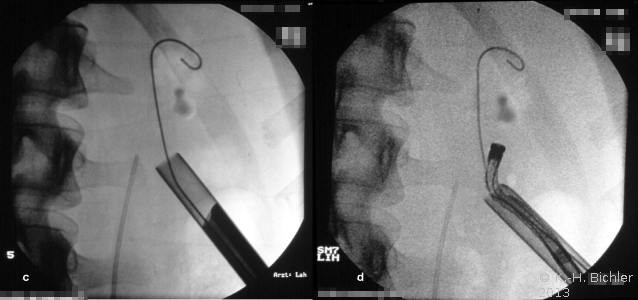

Zur perkutanen Entfernung von Steinen aus dem Nierenbeckenkelchsystem stehen auch flexible Instrumente zur Verfügung (Abbildung 8).

Die Abbildung zeigt das perkutane Vorgehen bei einem Nierenbeckenkelchstein (Abbildung 9).

Bei Anwendung der perkutanen Methoden mit entsprechend miniaturisierten Instrumenten finden sich Steinfreiheitsraten von 58% bzw. bei Entfernung der Reststeine von 81%. Bei zusätzlicher Anwendung von ESWL liegen die Erfolgsraten bei 90% bis 100%